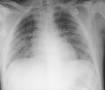

La radiografía de tórax muestra imágenes variables en función de la gravedad del cuadro. En las formas frustras, aparece un infiltrado fino que puede ser muy efímero en su duración. El aspecto característico de las formas graves está constituido por opacidades algodonosas, perihiliares, con predominio bibasal, cubriendo progresivamente la mayor parte de los campos pulmonares, con el aspecto típico del síndrome de dificultad respiratoria aguda.